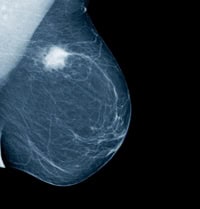

Mammogram with a cancerous tumour

Breast cancers that are detected early can often be treated with breast conserving surgery. Research shows that a course of radiotherapy after surgery for breast cancer significantly lowers the risk of the cancer recurring either in the remaining breast tissue or in lymph nodes.